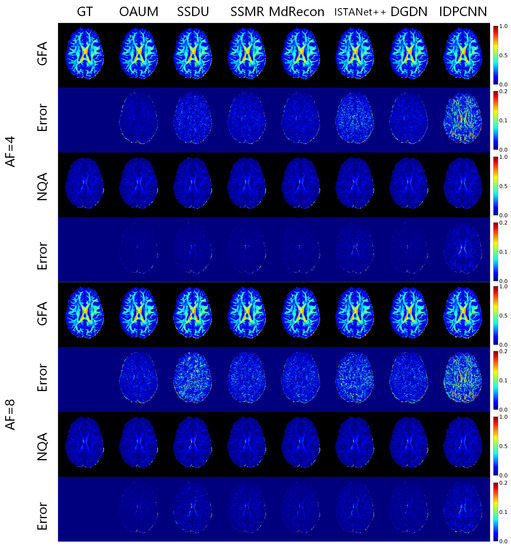

Based on the reconstruction of fiber orientation using HARDI, we calculated the generalized fractional anisotropy (GFA) and normalized quantitative anisotropy (NQA) under different acceleration sampling factors to characterize the diffusion of water molecules in tissues, as shown in Figure 7. The given GFA and NQA results, along with corresponding residual maps, indicate that all models except IDPCNN and ISTANet++ can reconstruct diffusion parametric maps well. Our OAUM model had the closest reconstructed GFA and NQA to the real results, with minimal residual values compared to the other models. Although the NQA image reconstructed by DGDN was close to our method, its reconstructed GFA image was slightly worse. Table 4 and Table 5 provide quantitative indicators that show that, regardless of whether it is at a 4-fold or 8-fold acceleration factor, the OAUM model obtained optimal quantitative evaluation results for both GFA and NQA, i.e., with the lowest RMSEs and the highest PSNRs and SSIMs. This implies that our proposed strategy ensures accuracy in HARDI parametric maps reconstruction under undersampling conditions.

Figure 7. The parametric maps estimated from DWIs at different acceleration factors.

Table 4. RMSE, PSNR, and SSIM of GFA reconstructed from different methods at different acceleration factors.

Table 5. RMSE, PSNR, and SSIM of NQA reconstructed from different methods at different acceleration factors.